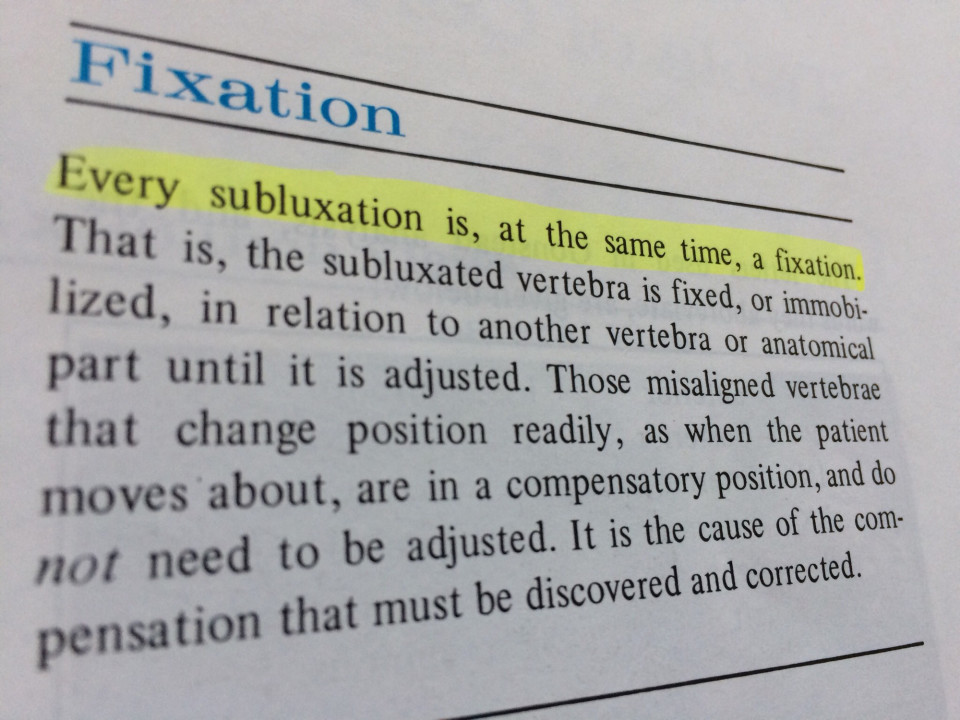

Fixation

Fixation